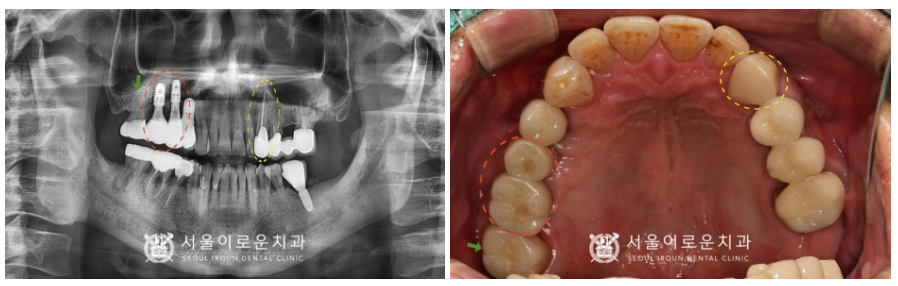

처음 내원 당시

환.자분의 파노라마 사진을 살펴보면

노란색 동그라미 표시의

위턱 왼쪽 송곳니(#23)이

충치로 인해 치아머리가 파절 되어 있어

신경치료 후 크라운 수복이 필요하였으며,

빨간색 동그라미 표시의

위턱 오른쪽 작은 어금니(#15)는

치아 뿌리가 파절되어 있어 발치 후

기존 상실된 첫 번째 큰 어금니(#16)와 함께

상악동 거상술을 동반하여

임플란트 식립이 필요하였습니다.

초록색 화살표의

위턱 오른쪽 두 번째 큰 어금니(#17)는

브릿지 제거 후 상태 평가 후

다시 크라운 수복 계획을

진행하기로 하였으며,

보라색 동그라미 표시의

아래턱 오른쪽 두 번째 큰 어금니(#47)는

타진 검사와 씹.는 검사에서

증.상이 있으며,

치아 뿌리 끝으로 병소가 관찰되어

신경치.료 후 크라운 치료가 필요했는데요.